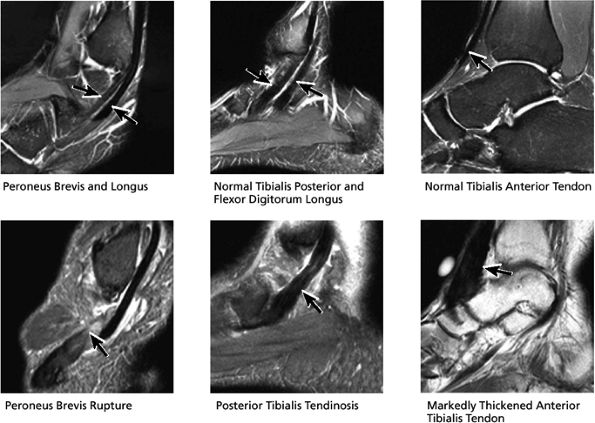

FIGURE 5.39 Tendons.

|